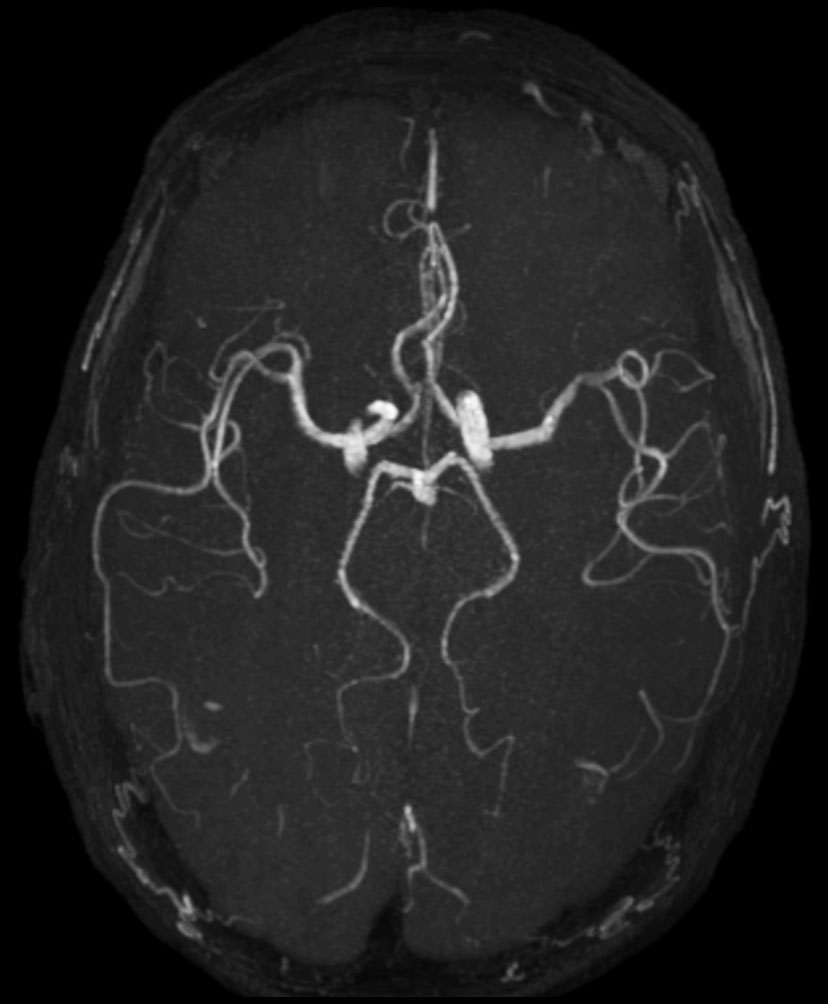

Brain imaging using ComforTone